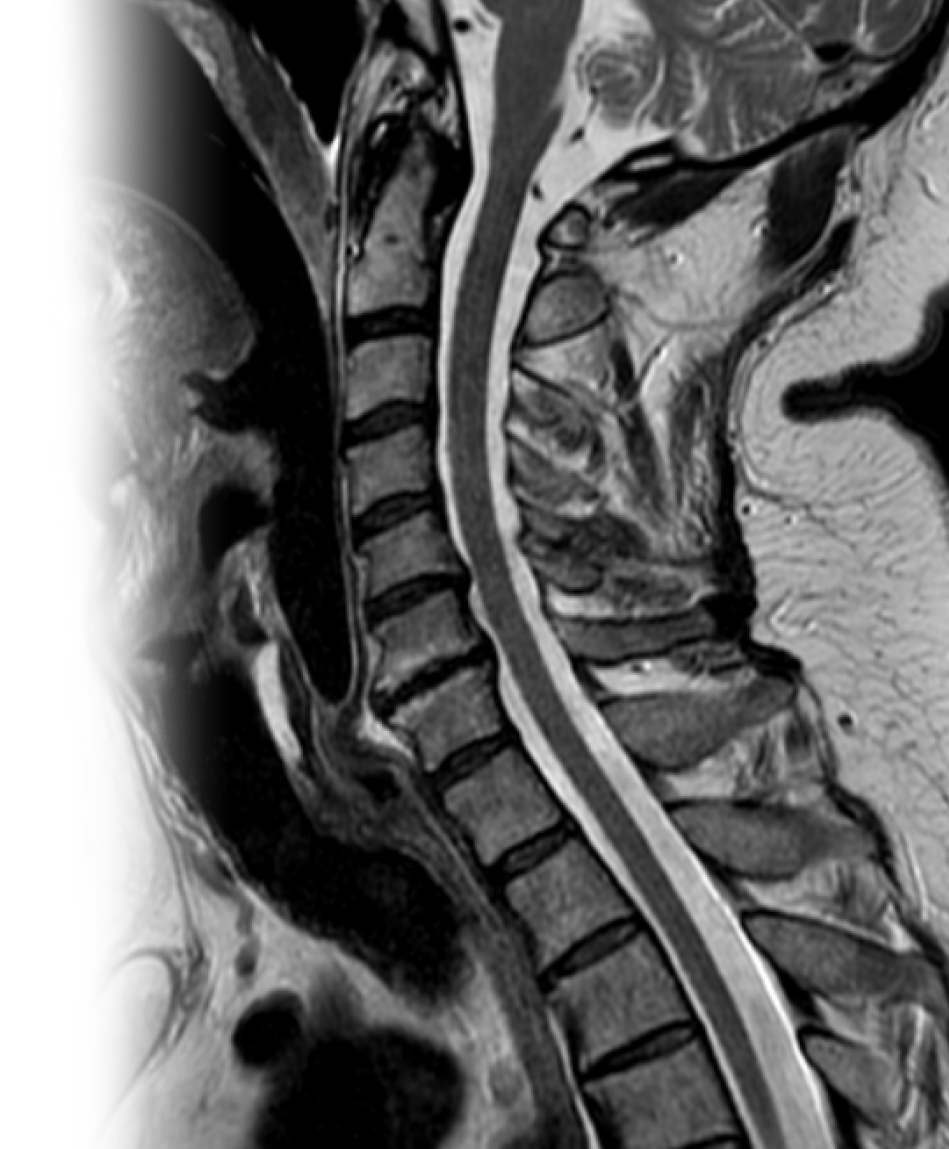

МРТ нескольких отделов позвоночника МРТ нескольких отделов позвоночника

МРТ нескольких отделов позвоночника

Магнитно-резонансная томография нескольких отделов позвоночника – важный метод исследования, который позволяет оценить состояние двух или трех отделов позвоночника.